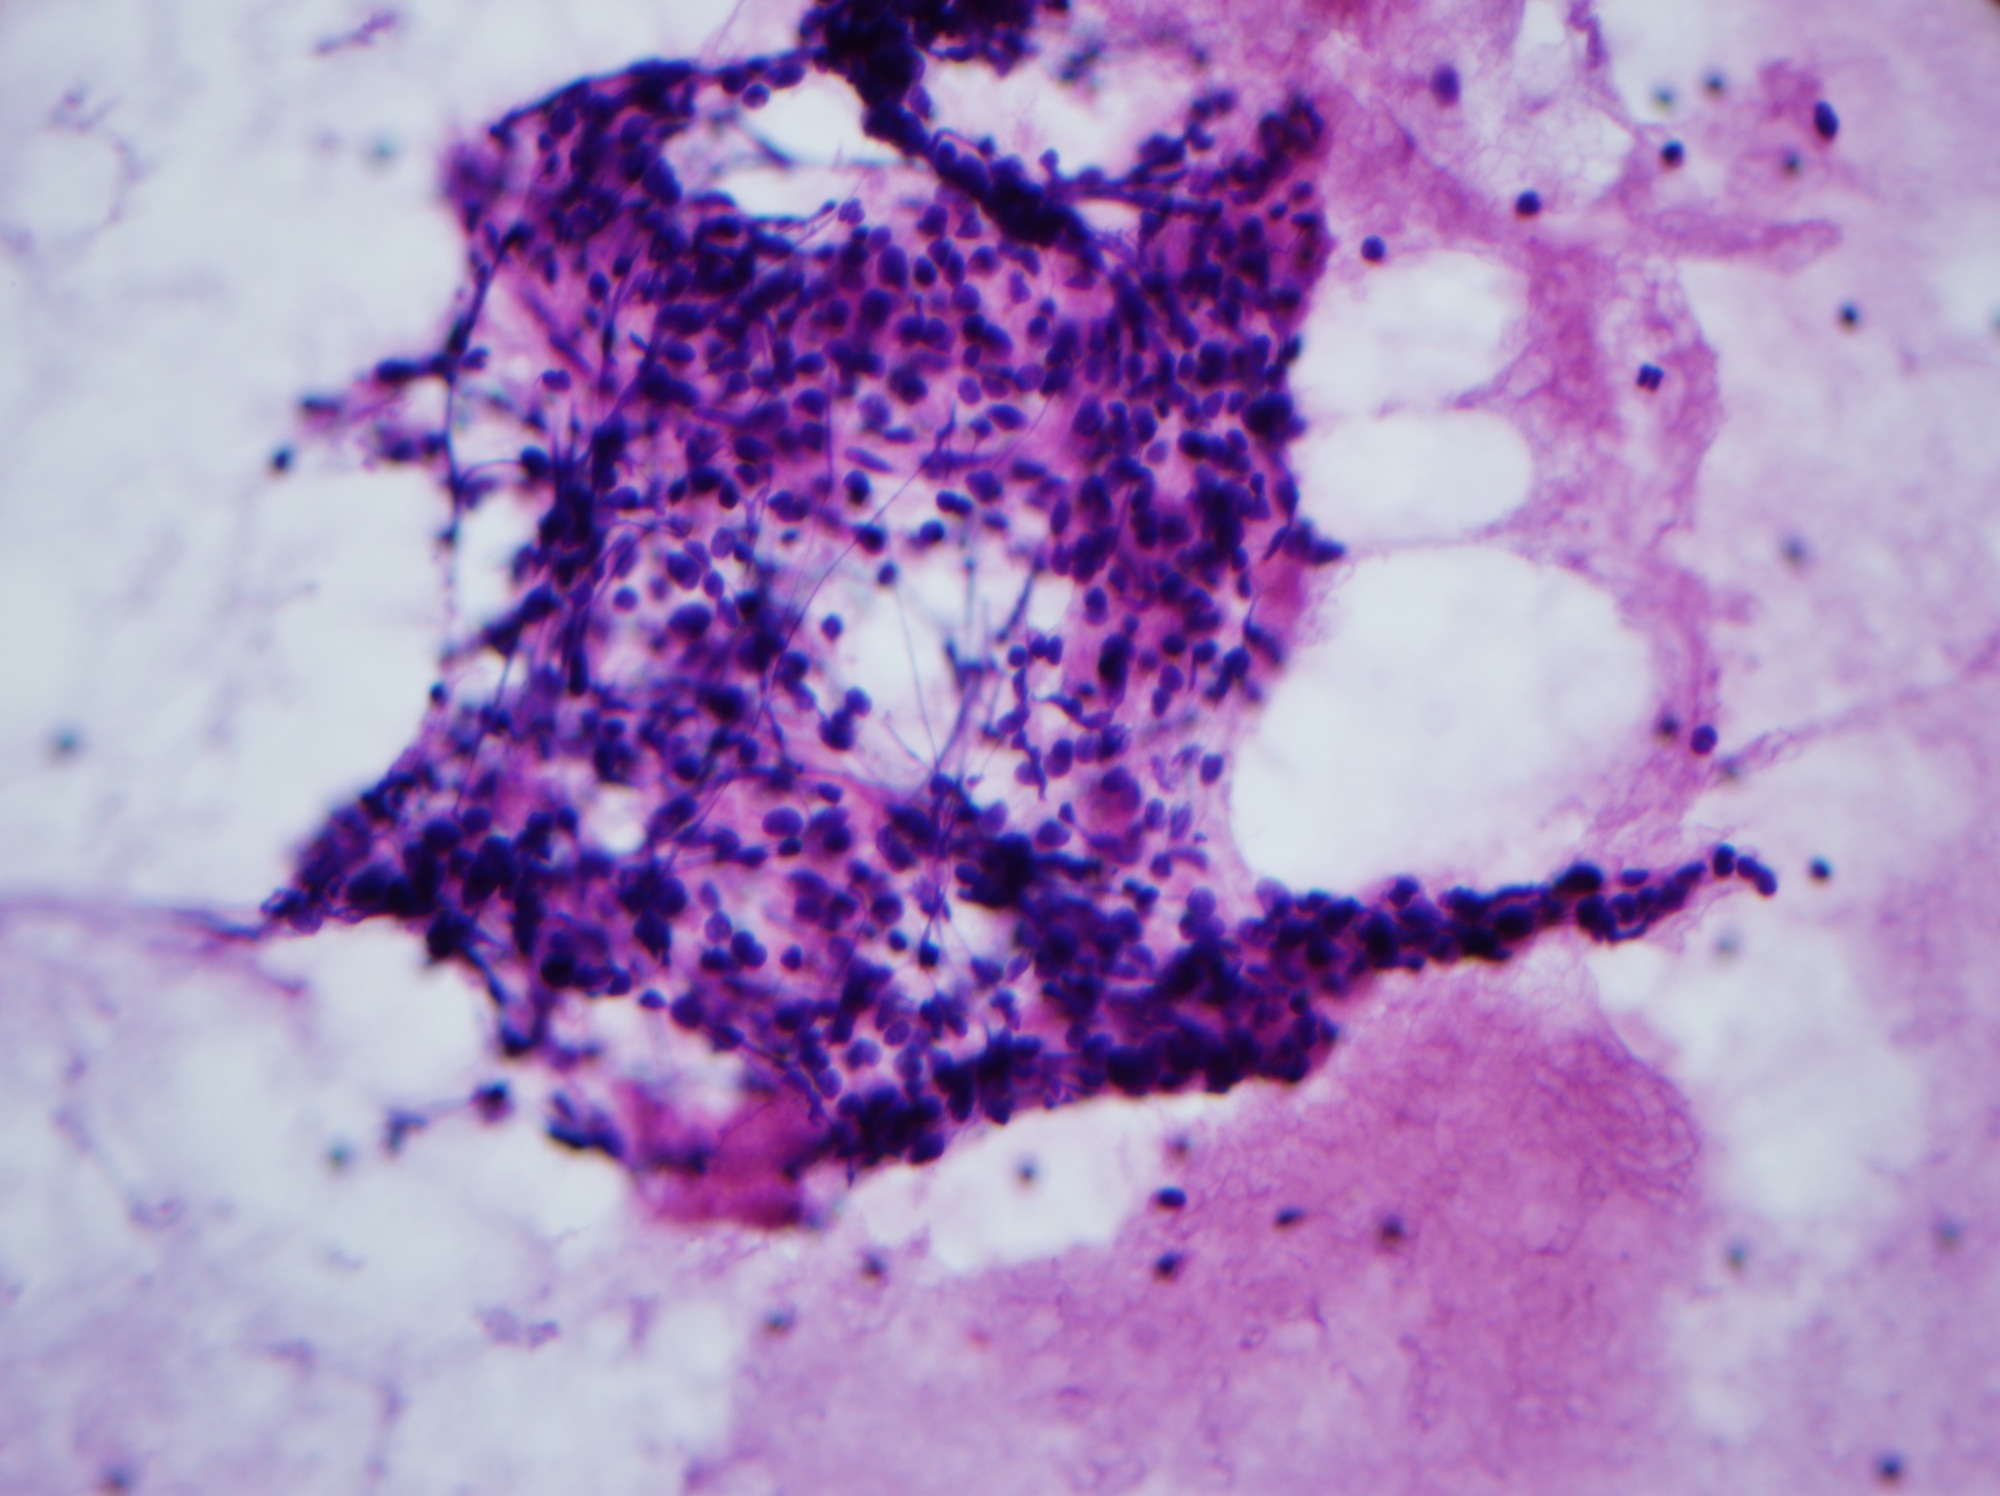

Accessory Tragus Pathology Outlines Accessory tragus is a relatively common congenital anomaly seen in ∼3 to 6 per 1000 live births. Incidence of 0.2 to 0.5%. Accessory tragus is a relatively common congenital anomaly seen in ∼3 to 6 per 1000 live births. Histological features of accessory tragus include a thin layer of stratum corneum with a rugated epidermis, presence of eccrine glands, and irregular spatial positioning of vellus hair follicles. Benign nonepithelial tumors arising from mesodermal tissue. Also has increased vellus hairs, but usually has other types of tissue (i.e. Also called accessory or supernumerary ear, accessory auricle, polyotia. An accessory tragus (at) is a benign congenital malformation caused by an aberration. Accessory tragus is a fairly common, benign congenital anomaly of the external ear that presents as a small elevation of the skin that is made up of skin, subcutaneous fat, and/or elastic.

From www.pathologyoutlines.com